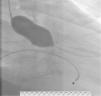

O ecocardiograma transtorácico (Figura 1) mostrou ventrículo esquerdo não dilatado, com ligeira hipertrofia do septo interventricular, com boa função sistólica global (FSG) e segmentar; válvula aórtica fibrocalcificada com gradiente transvalvular máximo de 74 e médio de 49mmHg e área calculada por equação de continuidade de 0,77cm2.